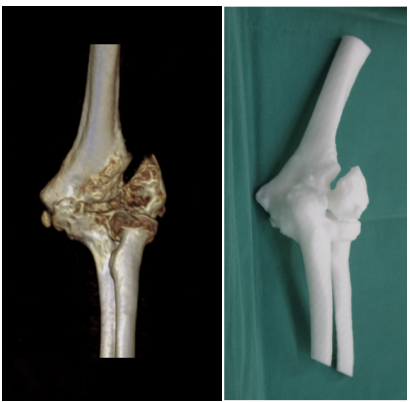

为了手术顺利进行,陈志伟主任团队发挥数字骨科团队的优势,利用3D打印技术打印出赵阿姨肘关节的模型,术前规划手术入路,截骨范围及假体按照位置,缩短手术时间,减少手术出血量,从而减少手术并发症,促进患者快速康复。

三维3D打印